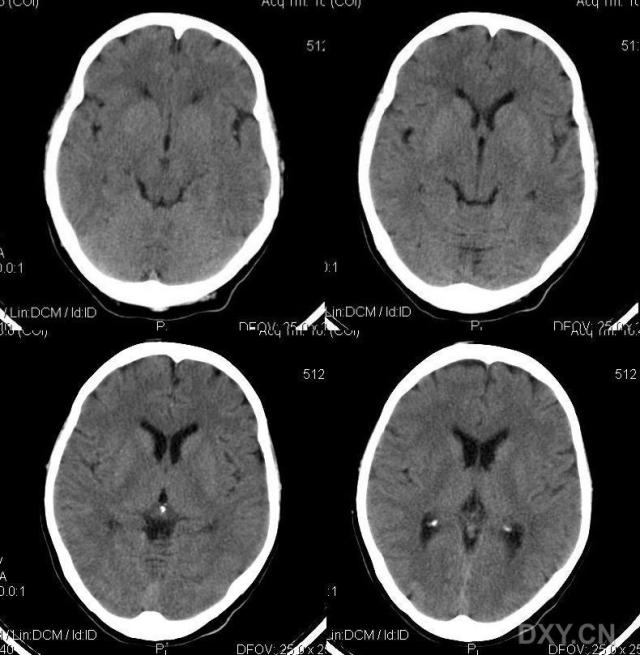

标题: CT11931:请看看有无异常!!

女性,62岁.头顶部不适,自述"头顶发凉"多年.

颅内无异常,骨窗呢?

颅内平扫未见异常。

颅脑平扫未见异常。

颅脑ct轴位平扫颅内未见明确异常。